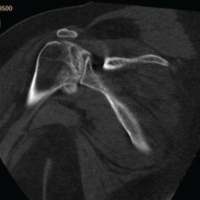

Despite this, his neurological function improved, allowing him to resume independent activities, including recreational baseball. He subsequently stopped attending follow-up visits. At 76 years of age, he returned to the previous hospital with progressive sputum production, worsening limb numbness and weakness, and gait disturbance. Physiological and neurological evaluation revealed bilateral lower-extremity weakness (manual muscle testing: digit extensor 4/4, iliopsoas muscle 3/2, quadriceps muscle 4/4, tibia anterior muscle 5/3, and extensor hallucis longus muscle 4/2), heightened patellar and Achilles tendon reflexes, and dysphagia. His cervical Japanese Orthopaedic Association (JOA) score was 6.5. Radiographs and computed tomography demonstrated vertebral osteolysis around the implant, absence of the right C6 screw, and air between the anterior implant surface and the esophagus (Fig. 2). Magnetic resonance imaging revealed a high-signal lesion from C5 to C7 on short tau inversion recovery sequences with spinal cord compression (Fig. 3). Upper gastrointestinal endoscopy revealed a 2-cm esophageal mucosal perforation with direct exposure of the cervical implant (Fig. 4).

Figure 3: (a-c) Computed tomography (CT) images showing osteolysis and screw disappearance. CT demonstrates osteolysis around the implant and the absence of the right C6 screw.